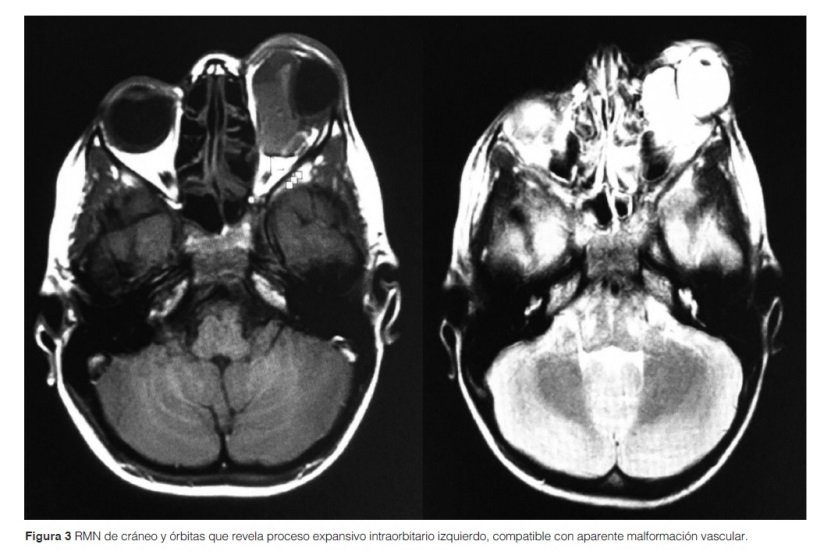

Al segundo día de internación, presentó un aumento de la intensidad del dolor local y de la proptosis que no cedió con analgésicos, por lo que se le realizó un drenaje quirúrgico de urgencia por endoscopía nasal rígida. Se evacuó gran cantidad de líquido hemático. Posterior al procedimiento se realizó una resonancia magnética nuclear (RMN) de cráneo y órbitas, que informó la presencia de un proceso expansivo intraorbitario izquierdo, evocando en primer lugar una malformación vascular, probable hemolinfangioma (Figura 3).

Es el segundo tumor vascular más común en la órbita, después del hemangioma capilar en niños, y se da en la primera década de la vida. Su localización puede ser intra y extraconal, incluso extraorbitario. El diagnóstico se establece mediante imágenes orbitales1-5. En la ecografía muestra una ecogenicidad heterogénea de predominio quístico. En TAC y RMN está peor definido que el hemangioma cavernoso, sobrepasando los límites de la órbita, como la fascia conal y el septo orbitario. Pueden captar contraste, pero menos que los hemangiomas1-2, en la RMN puede presentar una lesión multilolobulada o masa multiquística1-5. En el caso presentado, el paciente presentó proptosis ocular en varias ocasiones, secundaria a traumatismos contusos, con mejoría con antiinflamatorios y drenaje, no pudiendo esclarecerse con antelación el diagnóstico por la falta de estudios más sensibles y específicos como la RMN y la toma de material para biopsia.